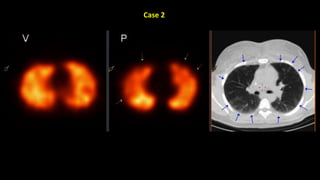

Modified Prospective Investigation of Pulmonary Embolism Diagnosis Criteria

Normal V/Q study

Ventilation [v] images on top row and perfusion [p] images beneath.

No defects are seen in either series.

Matched defects – multiple foci of nontracer uptake seen in ventilation and

perfusion series. Images reveals that the defects are well matched for position on

both series.

Perfusion defect (wedge-shaped peripherally) seen on perfusion imaging

which is not replicated on ventilation imaging.

This suggests a high probability for the presence of pulmonary embolus.*

Case 1

Case 2